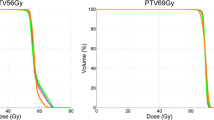

Both GPR (AAPM TG218 and 2% 2 mm local normalization) box plots are shown in Fig. 2. The mean values obtained (all patients) were 99.4% (95.8–100%), 97.8% (93.2–99.9%), and 96.6% (90.3–99.9%) for TOMO, VE-HD, and SYN plans, respectively. Those for the local 2% 2 mm GPR were 89.2% (80.2–99.9%), 86.9% (79.0–95.0%), and 84.7% (77.3–94.8%) for TOMO, VE-HD, and SYN plans, respectively.